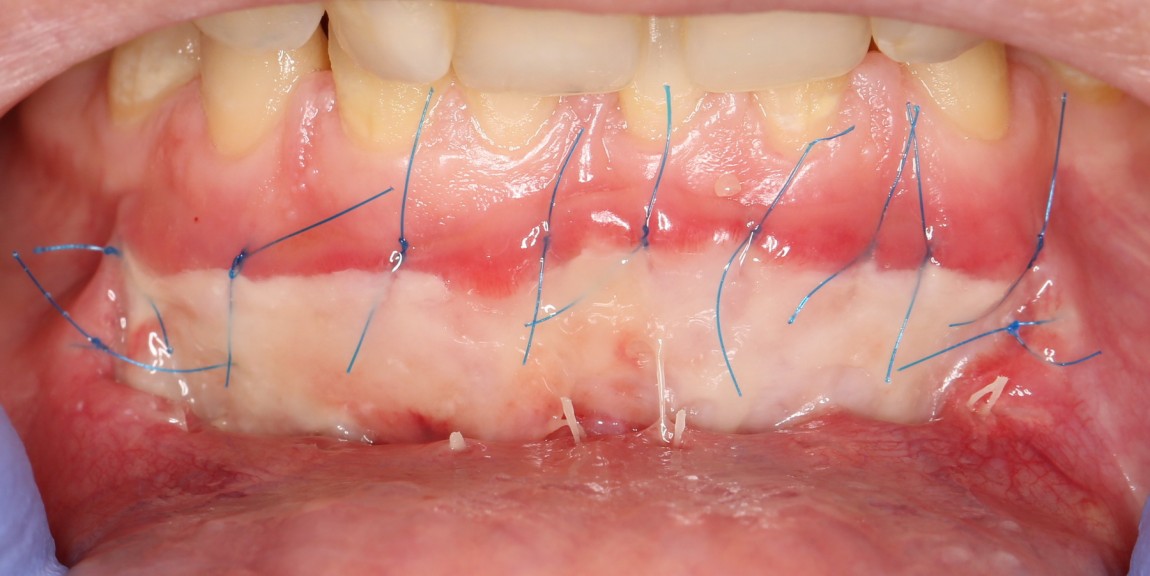

Матрица фиксируется, в первую очередь, к надкостнице, потом тем же вколом подцепляется слизистая оболочка. Получаются вот такие стежки:

Это как раз тот наглядный пример, где показана вся суть хирургии — мы больше шьем, чем режем.))

Операция закончена: